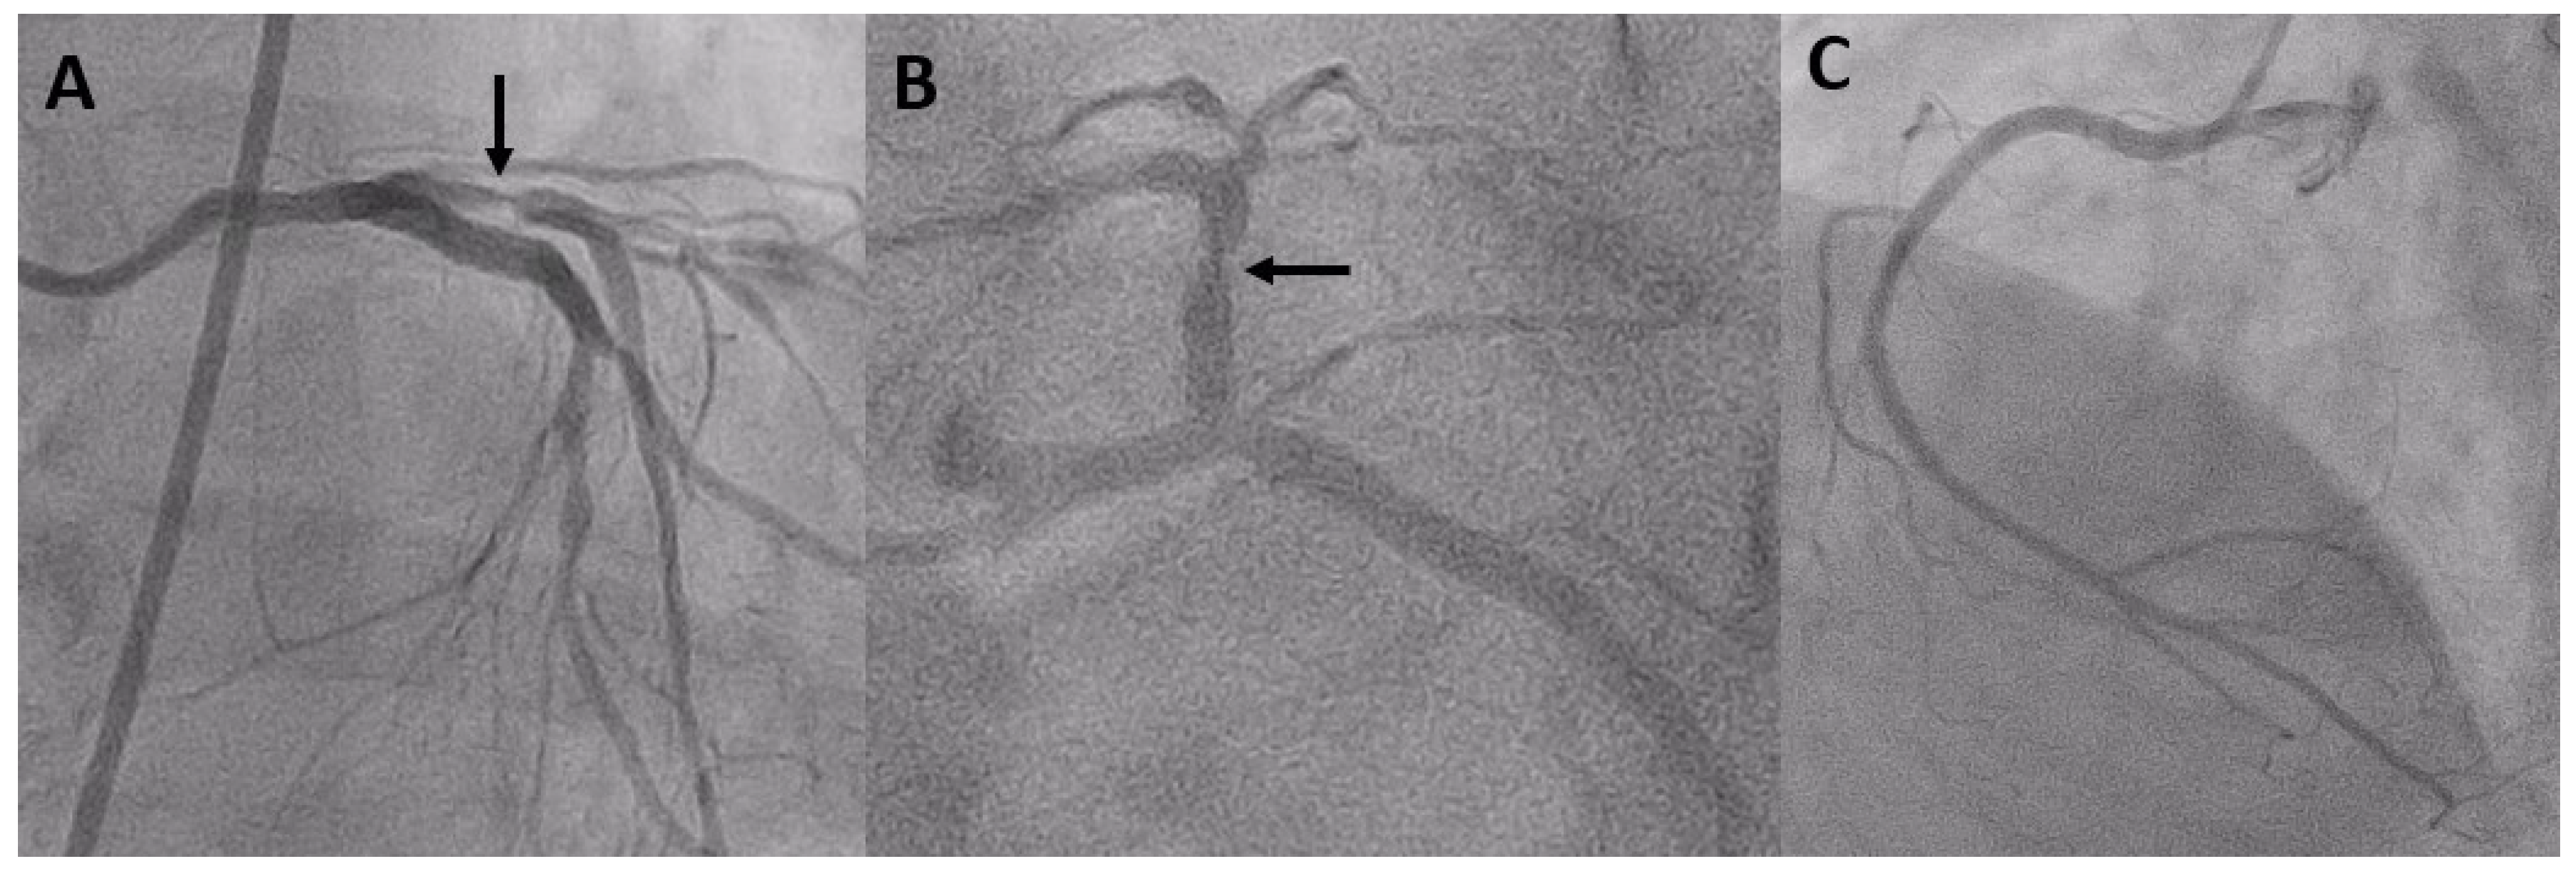

The Best Strategy for the Black Hole Phenomenon between Intravascular Ultrasound and Optical Coherence Tomography

- Castagna, M.T.; Mintz, G.S.; Weissman, N.; Maehara, A.; Finet, G.; Waksman, R. "Black hole": Echolucent restenotic tissue after brachytherapy. Circulation 2001, 103, 778. [Google Scholar] [CrossRef] [PubMed]

- Hirose, M.; Kobayashi, Y.; Leon, M.B. Echolucent neointimal hyperplasia "dark wall" after sirolimus eluting stent implantation. Heart 2004, 90, 1143. [Google Scholar] [CrossRef] [PubMed]

- Goto, K.; Shiode, N.; Shirota, K.; Fukuda, Y.; Kitamura, F.; Tominaga, K.; Kato, Y.; Miura, H.; Inoue, K.; Nobuyoshi, M. Pathological finding of sirolimus-eluting stent (SES) restenosis lesion with black hole appearance on intravascular ultrasound. Circ. J. 2009, 73, 1969–1971. [Google Scholar] [CrossRef] [PubMed]

- Otsuka, Y.; Murata, T.; Kono, M.; Imoto, H.; Koyama, T.; Nakamura, K.; Kadama, S.; Noguchi, H.; Saito, T. Black hole restenosis after drug-eluting stent implantation for in-stent restenosis: Potential mechanism and optimal strategy. Heart Vessels 2015, 30, 682–686. [Google Scholar] [CrossRef] [PubMed]

- Kurita, T.; Terashima, M.; Suzuki, T. Serial optical coherence tomography imaging of the “black-hole” phenomenon by intravascular ultrasound following sirolimus-eluting stent implantation. EuroIntervention 2012, 7, 1480–1481. [Google Scholar] [CrossRef] [PubMed]

- Landmesser, U. Optical coherence tomography (OCT) evaluation after coronary stenting: The "black hole" and other low OCT signal-intensity areas. EuroIntervention 2012, 7, 1367–1371. [Google Scholar] [CrossRef] [PubMed][Green Version]